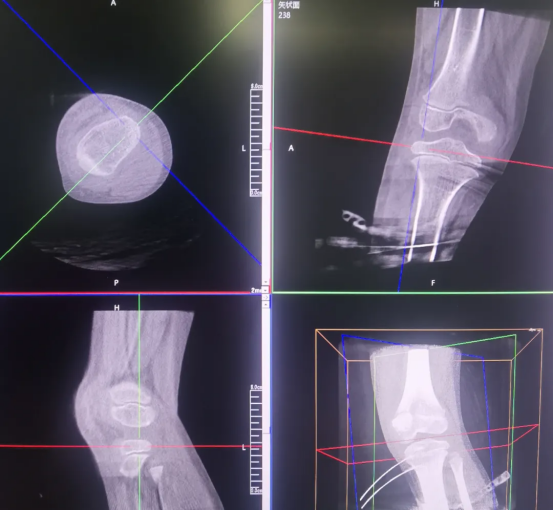

Perlove Medical’s 3D C-arm performs postoperative scans to verify screw placement from multiple dimensions: the relationship between the screws and the epiphyseal line

, any loosening or displacement and whether the femoral and tibial mechanical axes are approaching balance. If any subtle issues are detected, timely adjustments can be made to ensure optimal screw fixation. This postoperative 3D verification eliminates the observation blind spots in 2D imaging and serves as the final safeguard for surgical outcomes and long-term skeletal health.